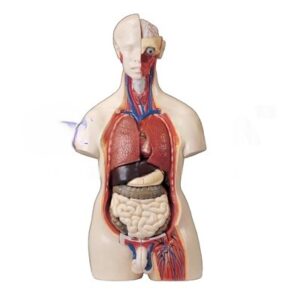

Related Products

Related products